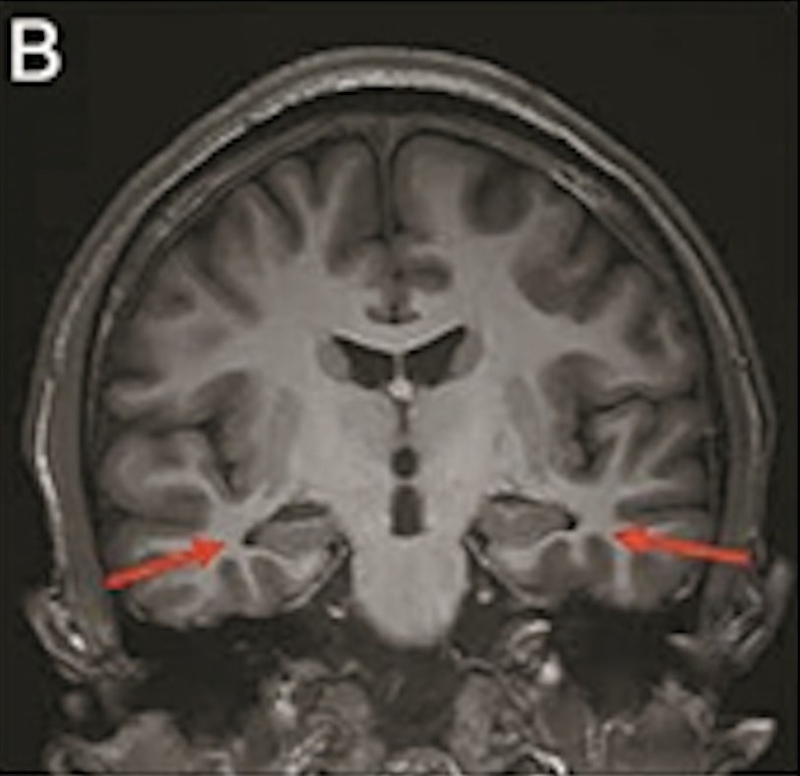

最年轻的19岁阿兹海默症男子脑部扫描结果:

▲19岁阿兹海默症(认知障碍症/脑退化症)男子脑部扫描结果。北京青年报

该名19岁男子到医院接受多项检查,包括脑脊液指标检测及正电子扫描。结果显示,他出现轻度脑萎缩等症状,最终被临床诊断为“阿兹海默症”。